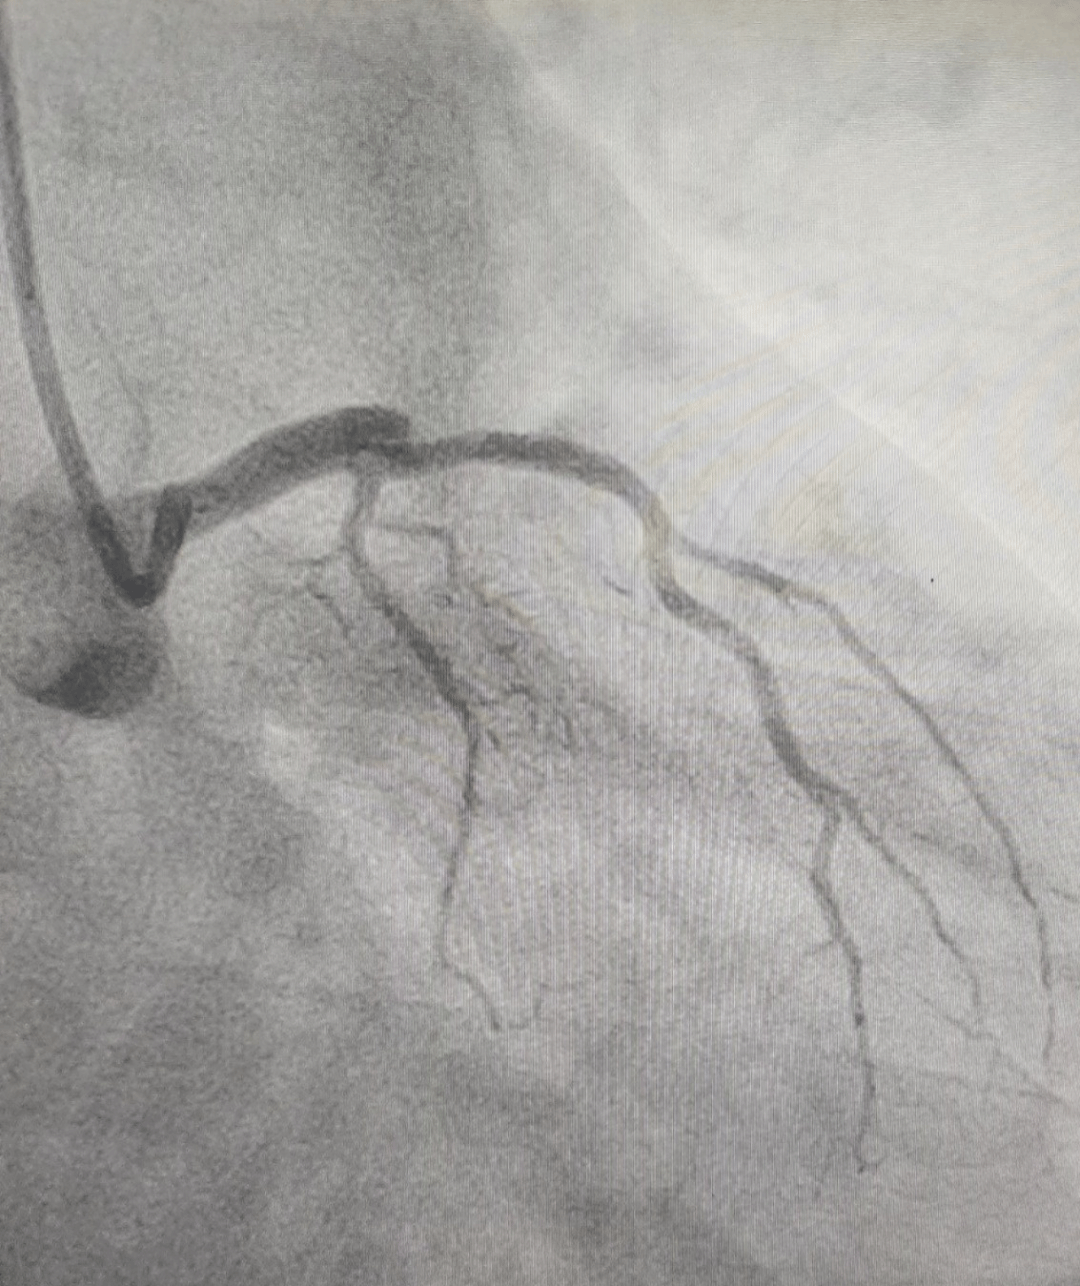

手术间内,铅衣加身,监护仪的滴答声与术者简短有力的口令声交织。冠脉造影精准锁定罪犯血管,导丝顺利通过,球囊精准扩张,一枚支架被准确植入闭塞段。患者进入导管室到血管开通 仅用时11分钟。术后,患者胸痛症状缓解,生命体征趋于平稳,被安全转运至CCU。

治疗前VS治疗后